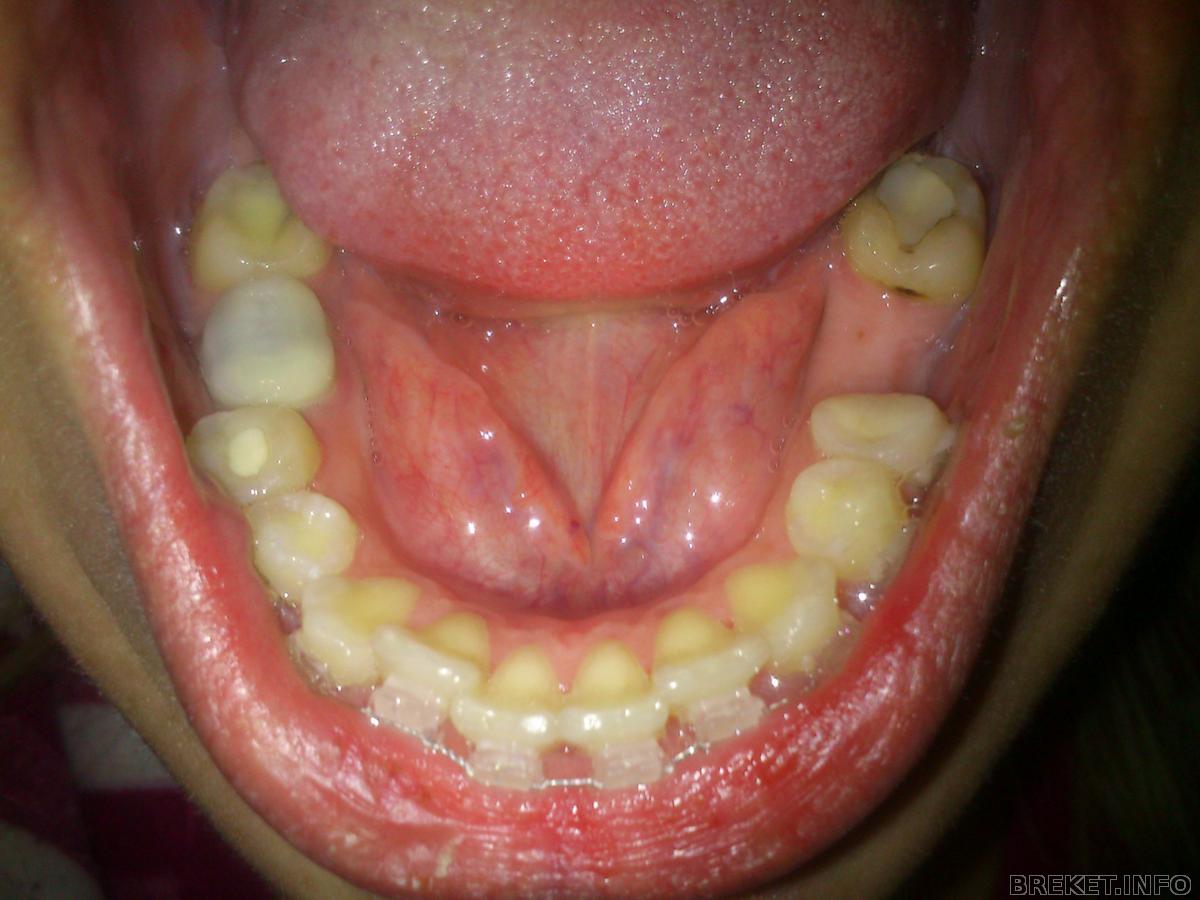

Все прошло очень быстро и совершенно безболезненно. Я так и не поняла почему многие боятся расширителя??? когда мне наклеили ВЧ дали отдохнуть минут 5 потом принялись за НЧ доктор все делала сама и паралельно все рассказывала все то что я уже знаю от вас ))) про уход про еду про боли ))) короче чуство конкретной стянутости я почуствовала в тот же момент как она натянула дугу... сразу мне все понравилось и я ехала домой и постоянно улыбалась. По дороге домой очень жалела что в машине на панели нет маленького зеркальца ))) на каждом светофоре отворачивала зеркало заднего вида чтоб полюбоваться на свою "практически голливудскую улыбку" )))))))) заехала к подруге похвасталась она сказала что мне идет и с брекетами я выгляжу моложе, муж сказал "Думал будет хуже" теперь он мне должен новые туфли за такую оценку

) попыталась пить теплый чай что то не приспособилась то обливалась то захлебывалась в итоге выпила через соломинку, попробовала есть мягкое мяско и мягкий хлеб не понравилось... потому как губы уже натирало и кайфа я не испытала... жесть началась очень быстро... если мне из поставили в 8 вечера то уже в 11 вечера я начала конкретно так ощущать боль на внутр стороне губ... но залепив все что можно воском пошла спать... проснулась от боли... везде... болят обе челюсти полностью особенно нижняя не могу даже разговаривать от боли... кароче адддд. желание есть пока не появилось как и чистить зубы...(обычно я иду чистить зубы еще с закрытыми глазами

Mexx, надеюсь что скоро! Кстати боли как резко начались так же резко и закончились... очень сильно болело только 2 дня а на третий день я уже могла кушать более менее нормально.